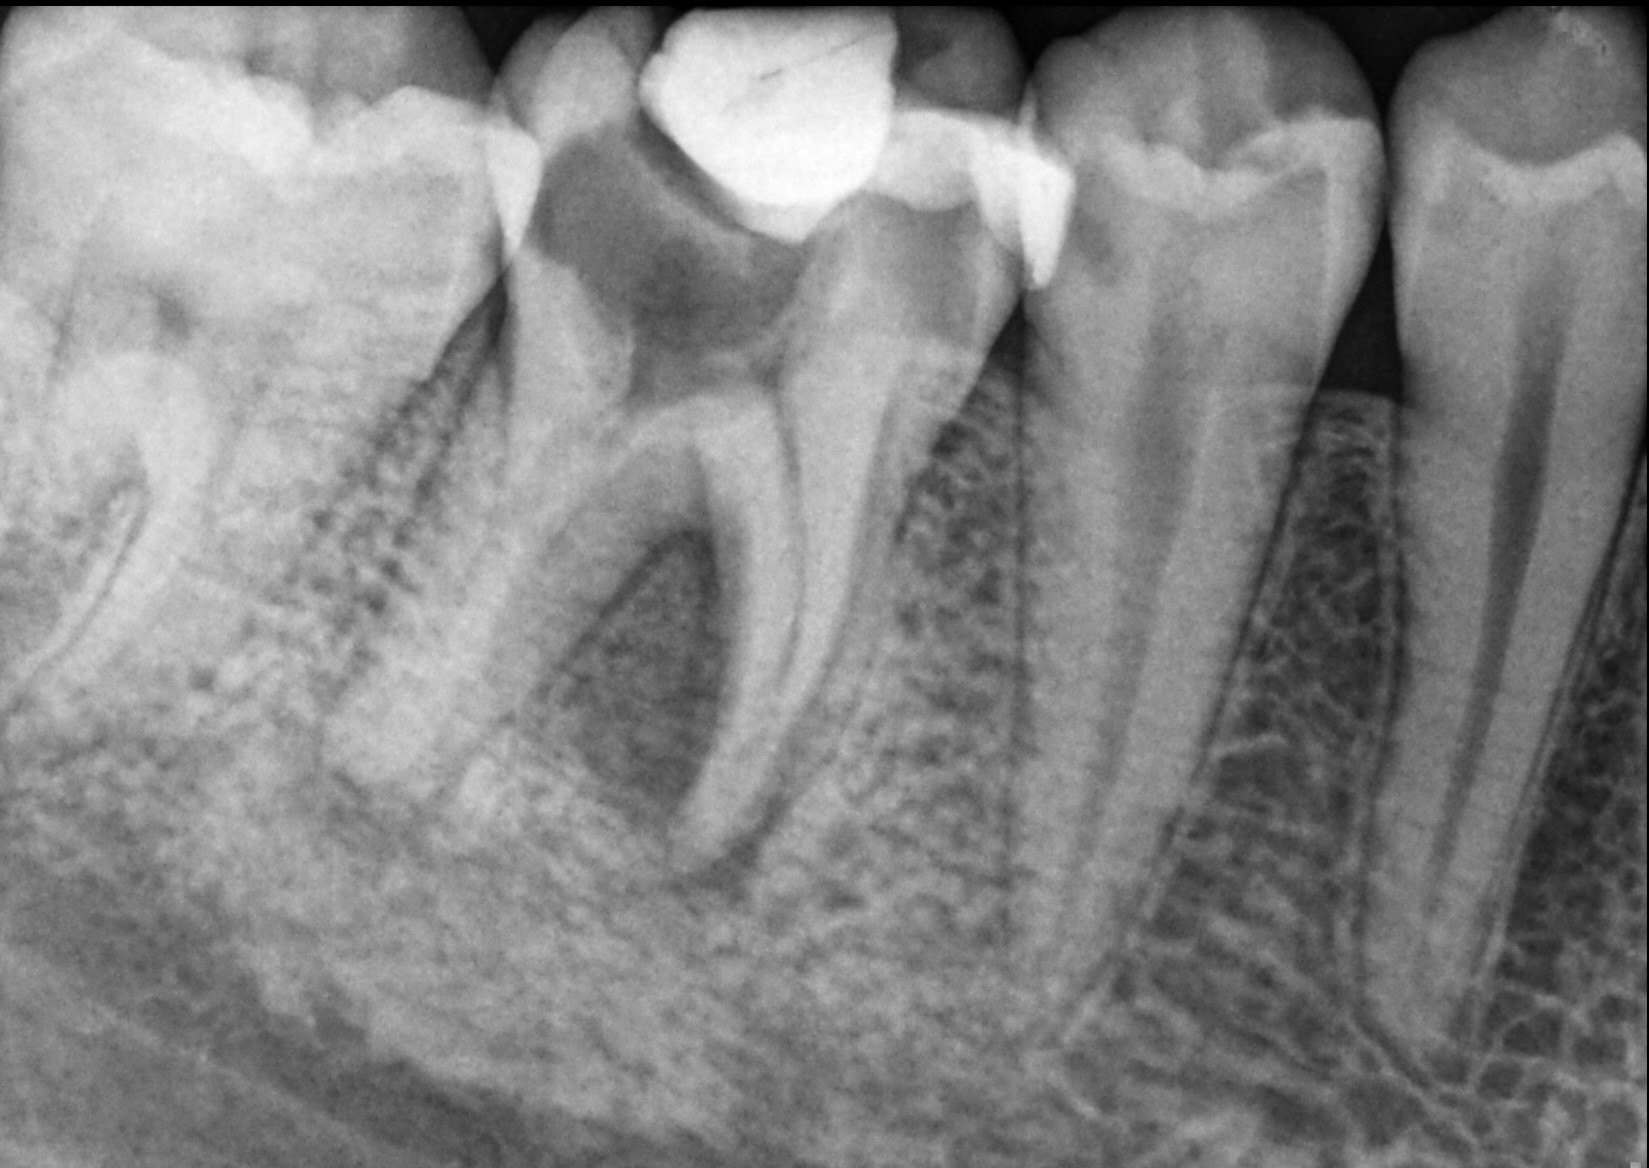

Diagnosis – Digital X-rays and 3D CBCT imaging for accurate assessment.

X-ray Gallery